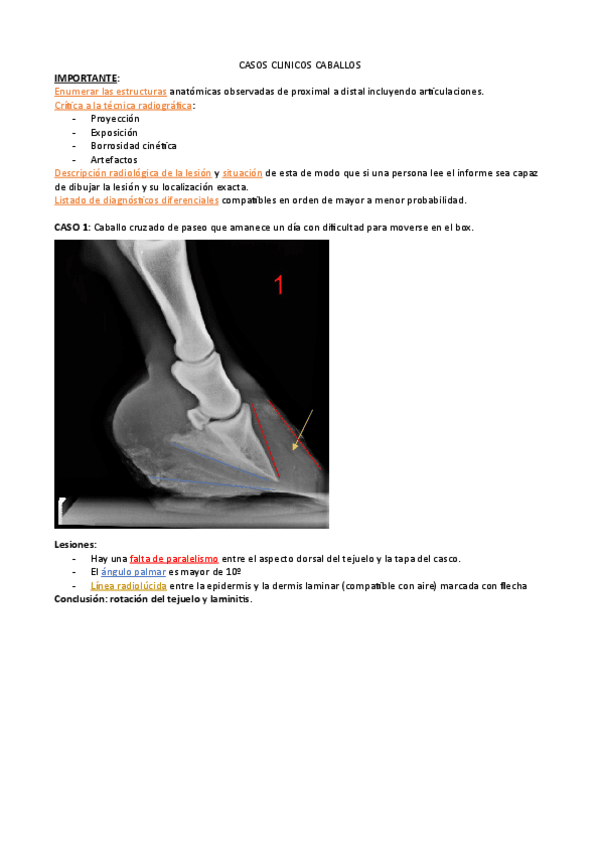

PRACTICAS-RX-EQUIDOS.pdf